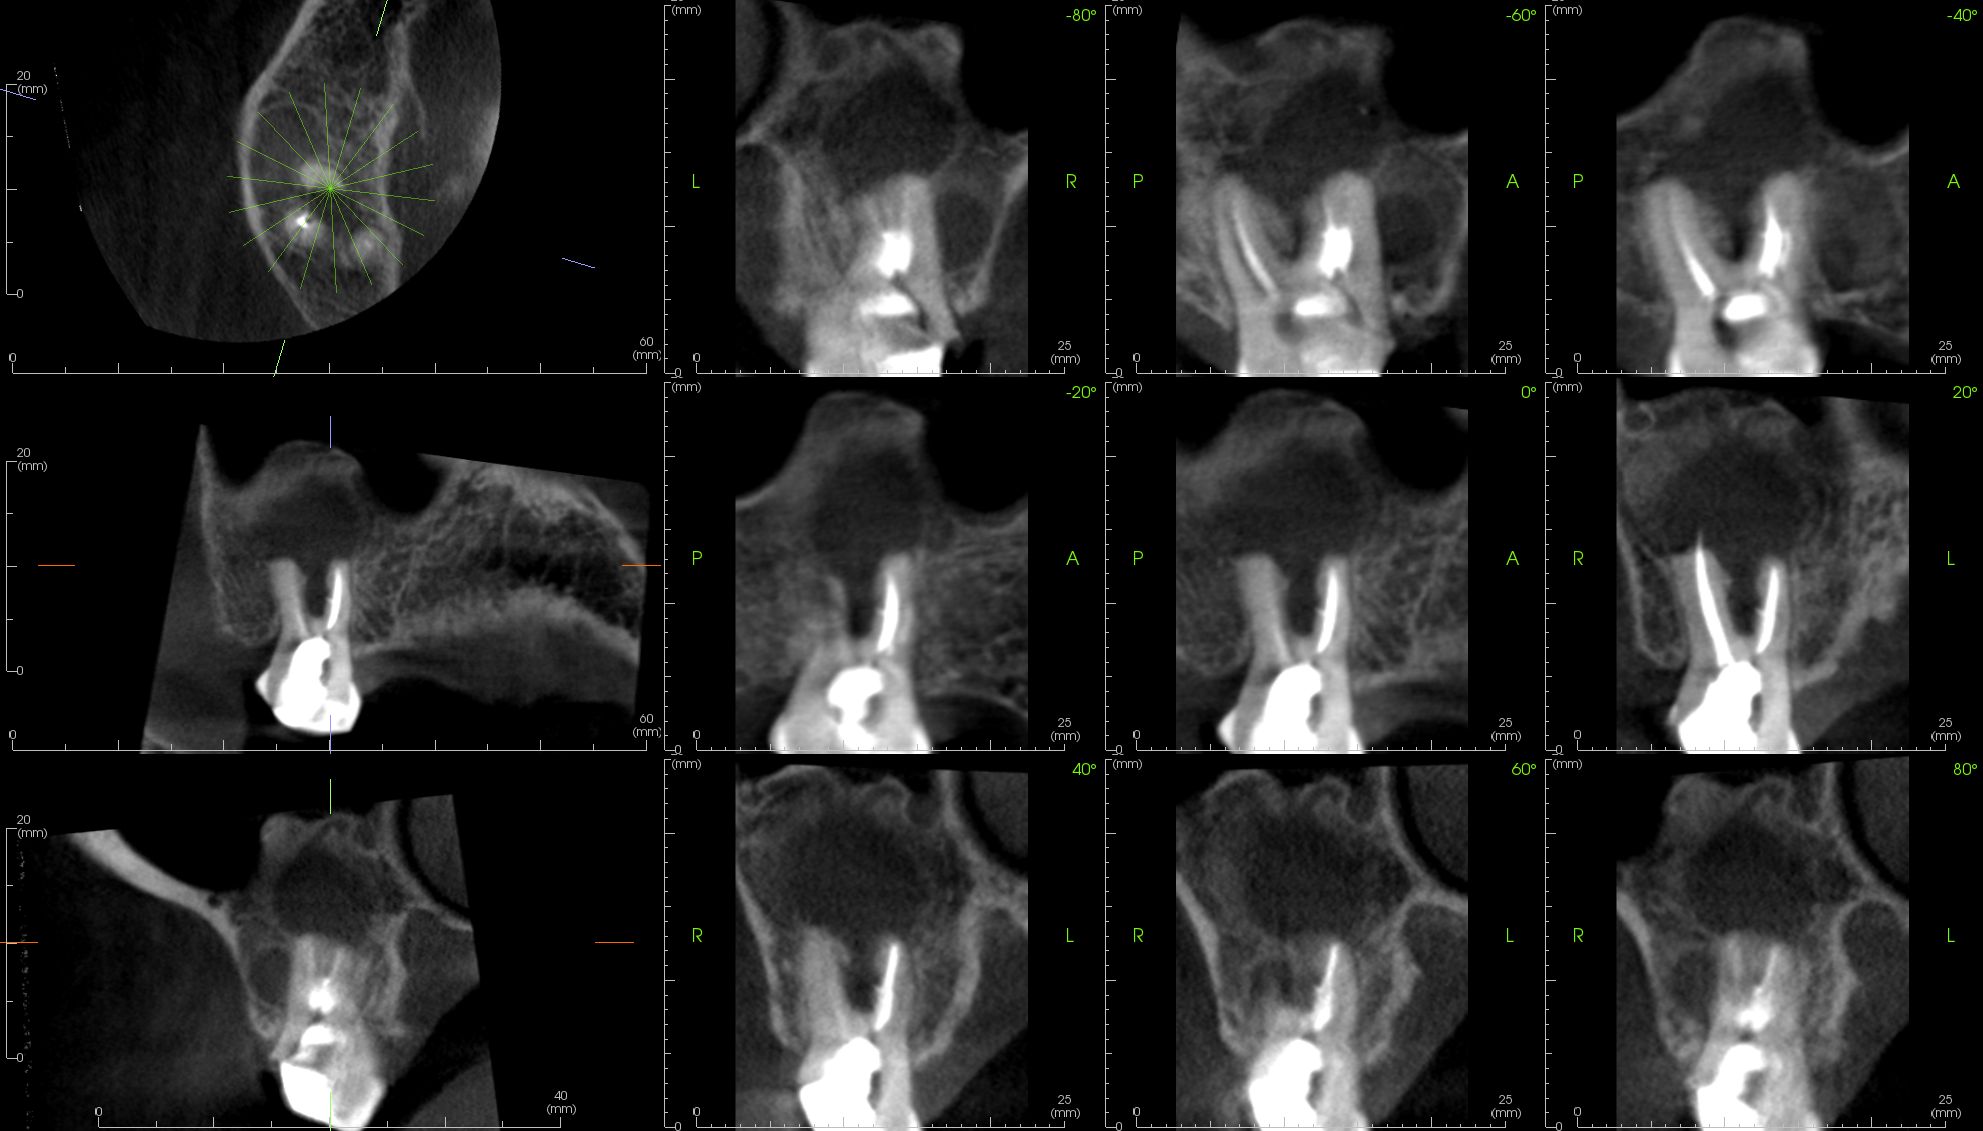

Image Portfolios visually communicate the imaging goals to you and your patient.